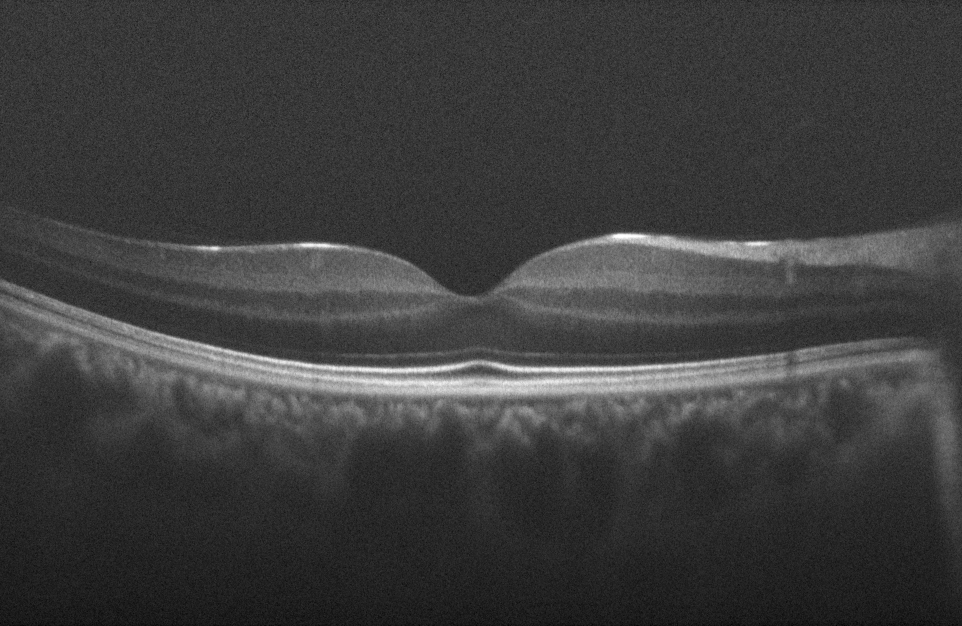

One important task in OCT image processing is the removal of speckle noise. Speckle is a fundamental property of the signals and images acquired by narrow-band detection systems like Synthetic-Aperture Radar (SAR), ultrasound and OCT. Not only the optical properties of the system, but also the motion of the subject to be imaged, size and temporal coherence of the light source, multiple scattering, phase deviation of the beam and aperture of the detector can affect the speckle [2]. Fig. 1(a) shows a sample retinal OCT image, highly degraded by speckle noise.

Fig. 1: (a) Sample retinal OCT image degraded by speckle noise, (b) Final result of the proposed method using 50 misaligned noisy retinal OCT images

Different numbers of images of the human retina in the central foveal region are considered for assessing the performance of the proposed algorithm. Fig. 1(a) shows a sample image of the dataset that is used here. As for other registration based methods, translation and rigid registration techniques available in ImageJ [17] software package are considered for comparison, since they are widely used in the literature and give reasonable performance.

Fig. 2 represents the improvement in the average SNR of the final image for different techniques, while Fig. 3 shows the improvement achieved in average CNR for different number of input images. Fig.1 (b) shows the final result of the proposed algorithm for speckle noise reduction using 50 misaligned noisy OCT input images.

One critical step in post-processing averaging/median filtering of the OCT images for noise reduction is the pre-selection of the set of images to be registered and averaged. This is due to the presence of μm𝜇𝑚\mu m-level features in the high resolution OCT images. During the imaging session, movement of the eye in 3 dimensions causes these features to appear/disappear between consecutive B-scans. In other words, fine features from very close locations come to focus, while some other features will go out of focus. This makes the pre-selection a necessary step at the beginning of the process. Using RPCA, this can be eliminated. As mentioned before, RPCA tries to divide the input set of data, here the stack of vectorized B-scans, into two components: one low-rank and one sparse. In this scenario, the algorithm looks for similar patterns in the data that are shared between different B-scans to extract the low-rank component while eliminating different patterns as being noise. In other words, without the need for pre-selection, the RPCA chooses the most common features as the ground truth and neglects the features that only appear in few B-scans and considers them as noise. Even though this can be achieved using simple averaging too, given enough number of images, still the main drawback is that naive averaging is indecisive about the common/uncommon features to be averaged causing it to have more blurred features. This is because the uncommon features are diffused to the rest of the data. The same analogy can be applied for elimination of blood vessel shadows between different B-scans. Fig. 4 displays close-ups of the original and filtered version of the input images using different techniques for comparison.